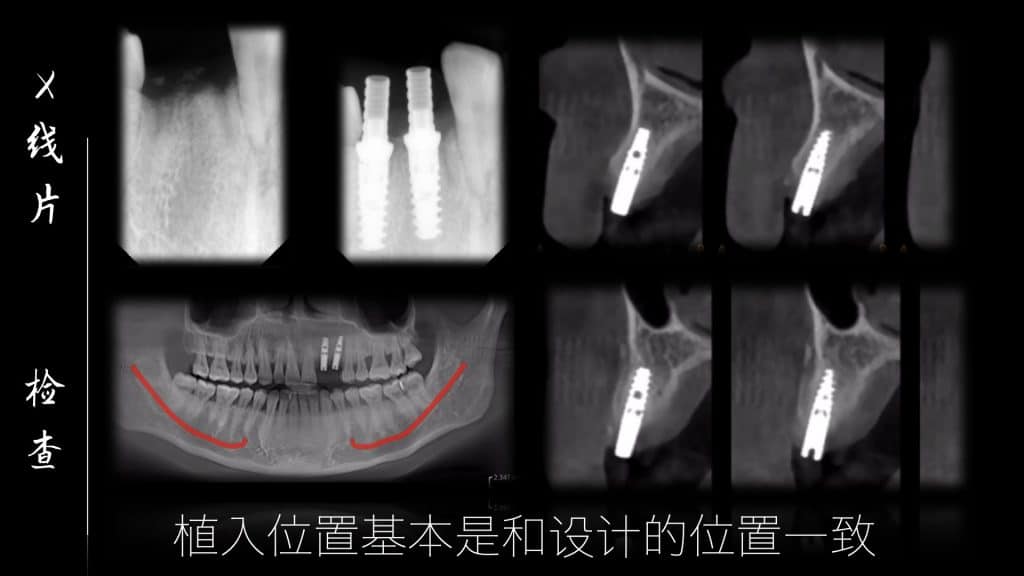

Before the start of this case, we did a fine digital design, including the design and production of temporary teeth, then CBCT matched the oral scan, designed the implant position, designed the incision method of our gums, and then implanted, and immediately repaired after completion, made a personalized gingival counter, and made a permanent restoration after 3 months.